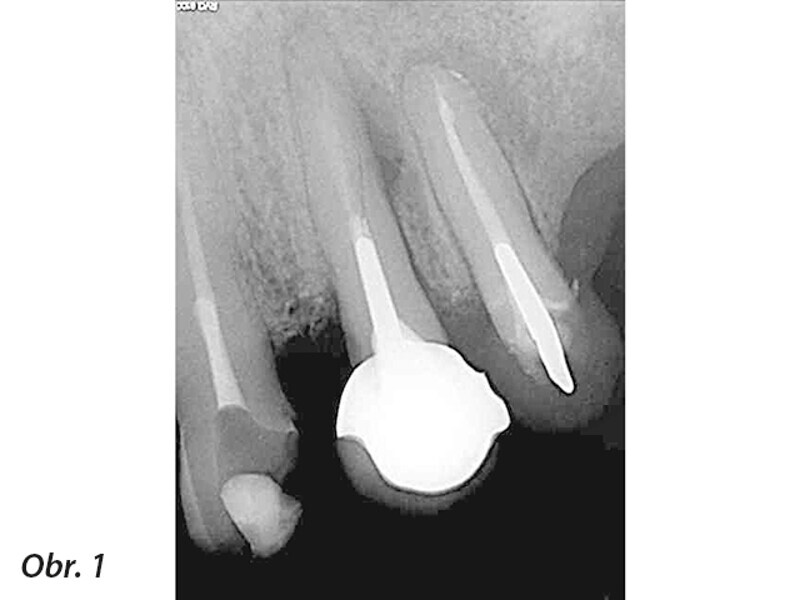

Periapikální léze implantátů a retrográdní periimplantitis – dva stavy nepříliš zdokumentované